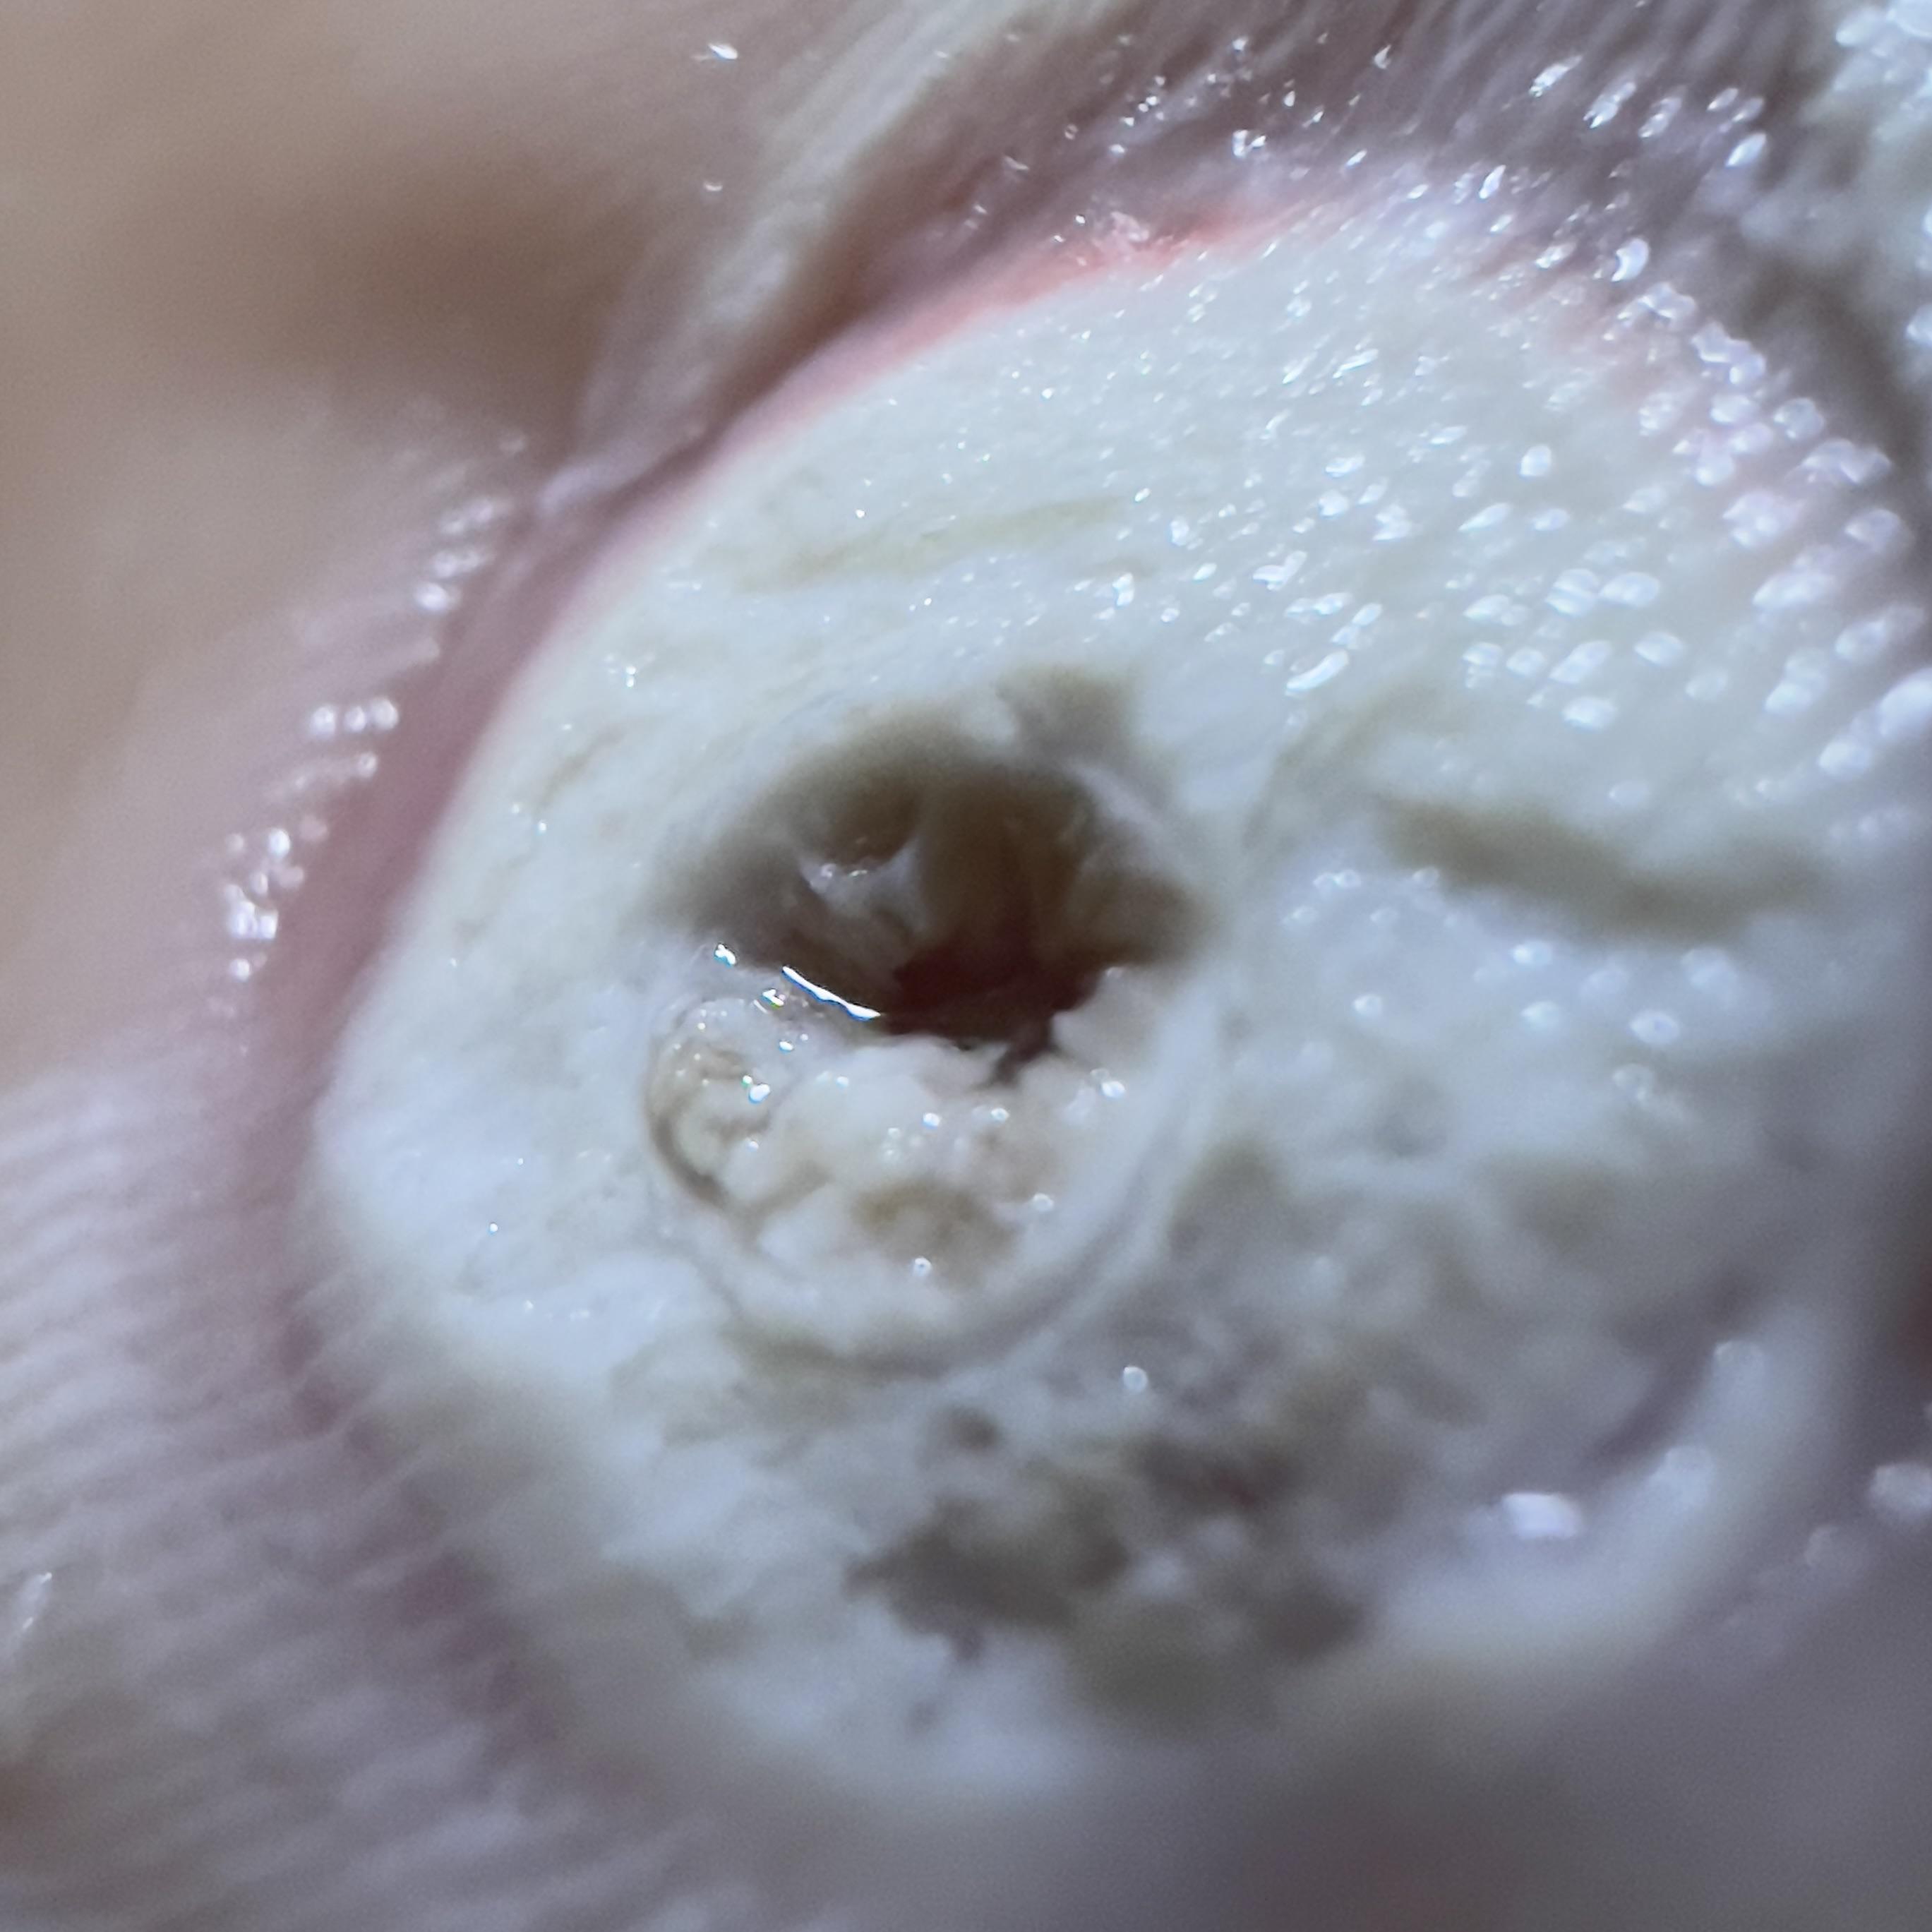

Plantar Wart Hole . plantar warts and palmar warts are noncancerous skin growths caused by a viral infection in the top layer of the. plantar warts, sometimes called verrucas, are a type of wart found on the sole of the foot or the toes, most. a plantar wart, sometimes called a verruca, is typically associated with the human papillomavirus (hpv) according. People can find salicylic acid for wart treatment in gel, liquid, or. treatment of a plantar wart, which grows inward, may leave a hole after wart removal. plantar warts are caused by an infection with hpv in the outer layer of skin on the soles of the feet. A health care provider usually diagnoses a plantar wart by looking at it or cutting off the top layer.

Plantar Wart Hole A health care provider usually diagnoses a plantar wart by looking at it or cutting off the top layer. A health care provider usually diagnoses a plantar wart by looking at it or cutting off the top layer. a plantar wart, sometimes called a verruca, is typically associated with the human papillomavirus (hpv) according. plantar warts are caused by an infection with hpv in the outer layer of skin on the soles of the feet. plantar warts and palmar warts are noncancerous skin growths caused by a viral infection in the top layer of the. treatment of a plantar wart, which grows inward, may leave a hole after wart removal. plantar warts, sometimes called verrucas, are a type of wart found on the sole of the foot or the toes, most. People can find salicylic acid for wart treatment in gel, liquid, or.